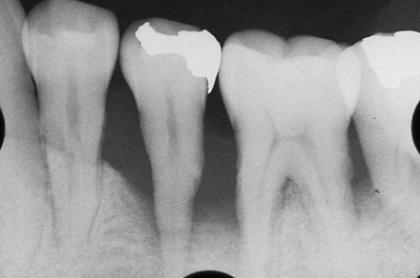

再生療法

Before

After

基礎データ 36歳・男性

治療期間 3年

治療費 270万円

主な治療

主な治療 歯周病治療(デブライドメント/歯肉縁下の歯垢、歯石、汚染歯根面、不良肉芽組織の除去)・抜歯・歯周再生療法(骨再生治療・rh-PDGF-BB)・暫間固定

治療計画

抜歯をしてインプラントを埋入する方が予知性は高いものの、口腔内の状況、患者さまの年齢、天然歯保存のご希望、経済的負担を考慮して、再生療法を選択しました。

難しい症例であるため高度なチャレンジにはなりますが、医療者自身も最良な治療法であると考えているため、あえて選択しました。